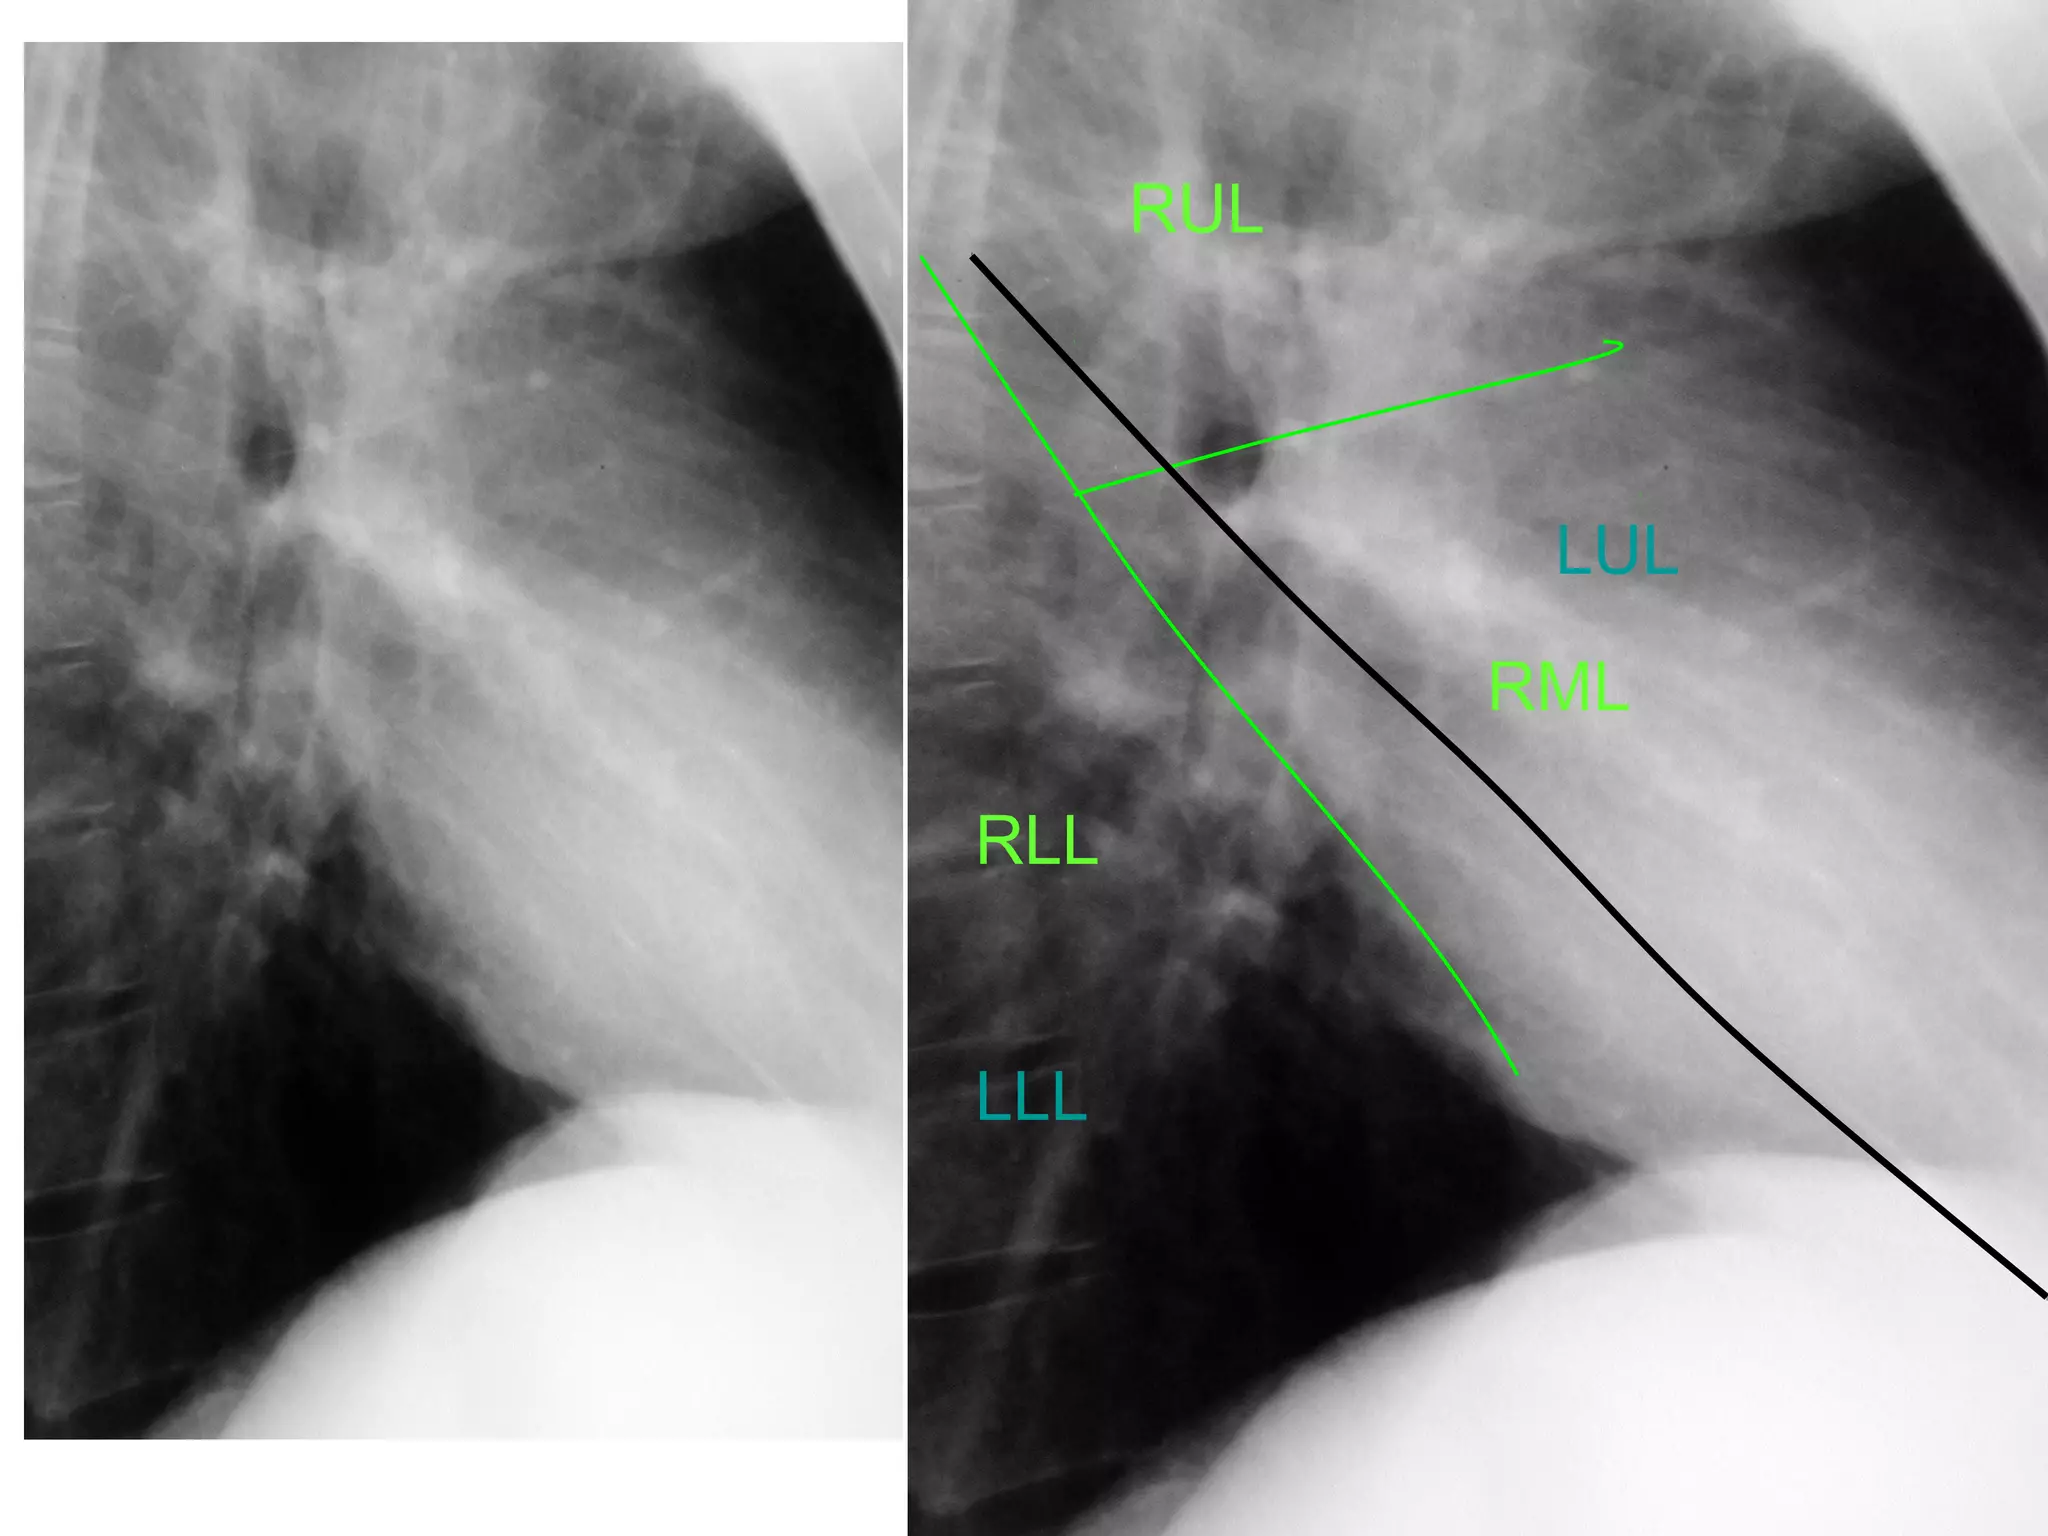

The fissures

The main fissures

The horizontal fissure is seen often incompletely

on PA film

The oblique fissures are seen on lateral film

commence posteriorly at the level of T4 or T5

passing through the hilum. The left is steeper

and finishes 5cm behind the anterior

costophrenic angle, where as the right ends just

behind the angle.

RUL

LUL

RML

RLL

LLL

The fissures The mainfissures The horizontal fissure is seen often incompletely on PA film The oblique fissures are seen on lateral film commence posteriorly at the level of T4 or T5 passing through the hilum. The left is steeper and finishes 5cm behind the anterior costophrenic angle, where as the right ends just behind the angle. Accessory fissures, the azygos fissure is comma shaped and nearly always right sided.

Right Oblique Fissure Horizontal Fissure Left Oblique Fissure

RUL LUL RML RLL LLL